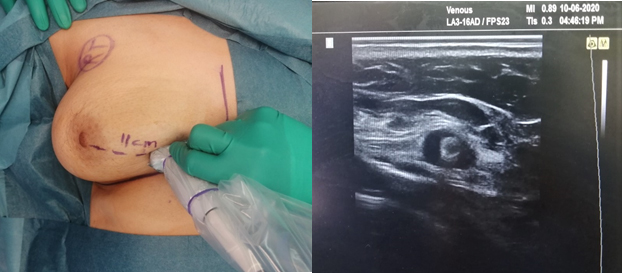

Ultrasound-guided lumpectomy

This is the preferred technique for surgeon who are trained to use the ultrasound machine inside the operating room to identify the non-palpable tumors. It is a one-step procedure that bypasses the wire insertion step, and more convenient to the patient. This technique provides the surgeon with immediate visibility and visual confirmation of the mass being removed. This technique also allows the surgeon to evaluate tumor margins after resection to ensure adequate margins and complete resection.

Research has shown that between 80% and 90% of breast lumps are clearly visible on ultrasound and can be removed using this technique. Many international surgical societies are now recommending for their trainees and members to receive a training course on the use of intraoperative ultrasound.